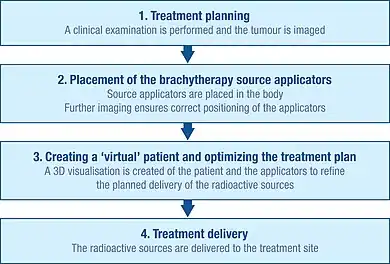

Initial planning

To accurately plan the brachytherapy procedure, a thorough clinical examination is performed to understand the characteristics of the tumour. In addition, a range of imaging modalities can be used to visualise the shape and size of the tumour and its relation to surrounding tissues and organs. These include x-ray radiography, ultrasound, computed axial tomography (CT or CAT) scans and magnetic resonance imaging (MRI).[1]: Ch. 5 The data from many of these sources can be used to create a 3D visualisation of the tumour and the surrounding tissues.[1]: Ch. 5

Using this information, a plan of the optimal distribution of the radiation sources can be developed. This includes consideration of how the source carriers (applicators), which are used to deliver the radiation to the treatment site, should be placed and positioned.[1]: Ch. 5 Applicators are non-radioactive and are typically needles or plastic catheters. The specific type of applicator used will depend on the type of cancer being treated and the characteristics of the target tumour.[1]: Ch. 5

This initial planning helps to ensure that 'cold spots' (too little irradiation) and 'hot spots' (too much irradiation) are avoided during treatment, as these can respectively result in treatment failure and side-effects.[29]

Insertion

Before radioactive sources can be delivered to the tumour site, the applicators have to be inserted and correctly positioned in line with the initial planning.

Imaging techniques, such as x-ray, fluoroscopy and ultrasound are typically used to help guide the placement of the applicators to their correct positions and to further refine the treatment plan.[1]: Ch. 5 CAT scans and MRI can also be used.[1]: Ch. 5 Once the applicators are inserted, they are held in place against the skin using sutures or adhesive tape to prevent them from moving. Once the applicators are confirmed as being in the correct position, further imaging can be performed to guide detailed treatment planning.[1]: Ch. 5

Creation of a virtual patient

The images of the patient with the applicators in situ are imported into treatment planning software and the patient is brought into a dedicated shielded room for treatment. The treatment planning software enables multiple 2D images of the treatment site to be translated into a 3D 'virtual patient', within which the position of the applicators can be defined.[1]: Ch. 5 The spatial relationships between the applicators, the treatment site and the surrounding healthy tissues within this 'virtual patient' are a copy of the relationships in the actual patient.

Optimizing the irradiation plan

To identify the optimal spatial and temporal distribution of radiation sources within the applicators of the implanted tissue or cavity, the treatment planning software allows virtual radiation sources to be placed within the virtual patient. The software shows a graphical representation of the distribution of the irradiation. This serves as a guide for the brachytherapy team to refine the distribution of the sources and provide a treatment plan that is optimally tailored to the anatomy of each patient before actual delivery of the irradiation begins.[85] This approach is sometimes called 'dose-painting'.

Treatment delivery